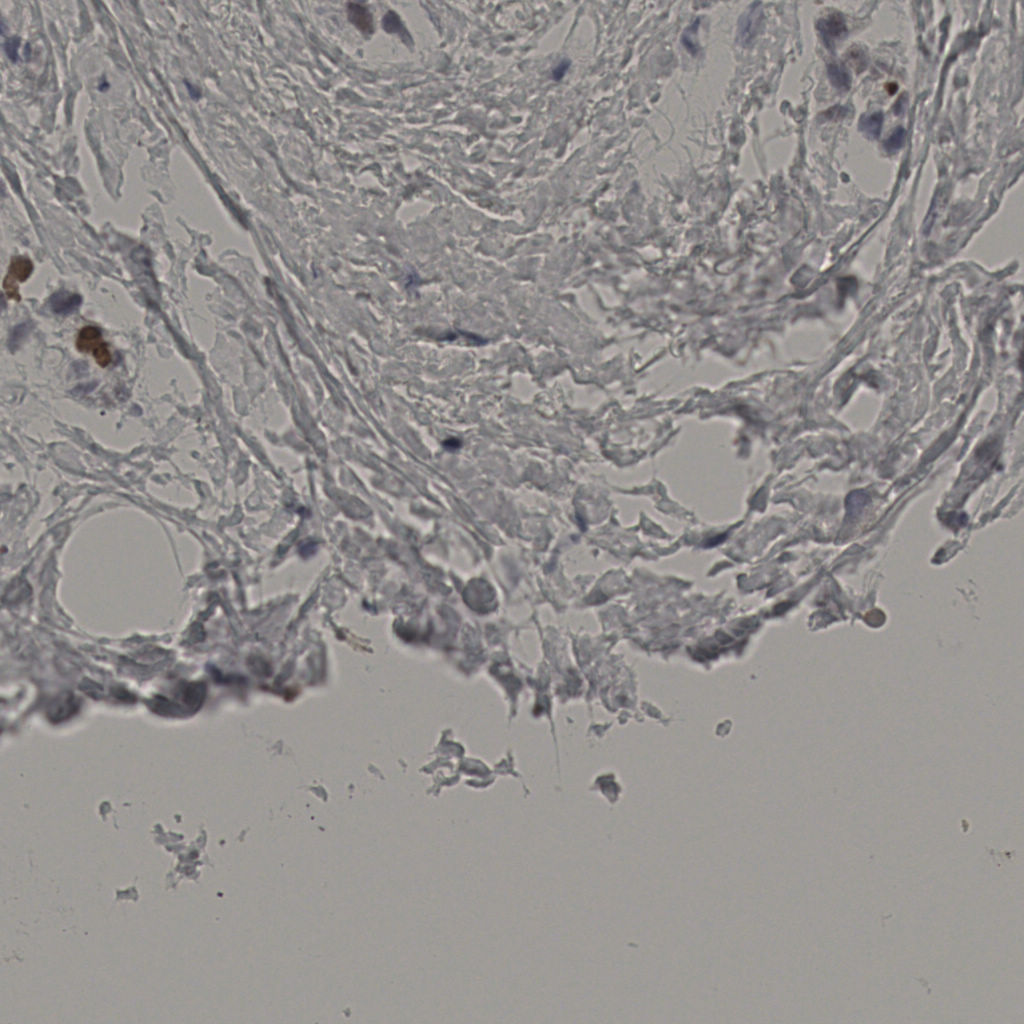

5.31%

Ki67 指数

阴 19502

阳 1093

标记后

标记前